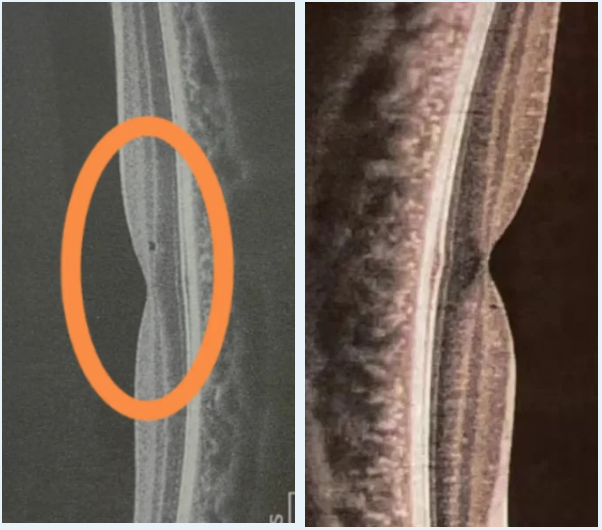

OCT定期复查时,偶见细小的裂隙样椭圆体带缝隙,或者椭圆体带粗糙。孩子可能没有感觉,也有可能出现眼前异常的光斑或者暗点,一旦观察到这种异常则需要停用,一般3~6个月之后恢复。

OCT定期复查时,偶尔可以看到黄斑区视网膜内层的小囊泡,孩子没有感觉,视力等指标一切正常。这种情况我们一旦发现也要停用红光,一般3个月自行恢复。

视网膜内层小囊泡在活体显微镜“星镜”下的表现

以上是我过去几年在门诊以及和其他医生交流时收集到的视网膜小囊泡案例,在2023年3月的公开培训课当中进行了分享。这些孩子矫正视力均完全正常,停用红光3个月之后再复查OCT,囊泡基本消退。